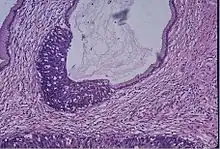

Cervical cancer is the fourth most common cancer for women with an estimated 340,000 deaths according to the World Health Organization (WHO).[27] HPV disease is the leading cause of cervical cancer, therefore making the HPV vaccine the primary prevention measure for the cancer. Screening with the Papanicolaou (Pap) test is consequently the second measure of prevention.[27] The test identifies cells that are precancerous, and are often credited for the reduced mortality.[28]

WHO encourage implementing population-based screening programs. There is a considerable range in the recommended age at which to begin screening around the world. The US does not follow a nation-wide program, and guideline recommendations differ, with some states recommend commencing screening at age 21 and others at 25; the intervals for testing also very, with intervals ranging from 3–5 years. The EU has guidelines for its member states when it comes to cancer screening, but they are not obliged to follow them as they are merely for assistance; it recommends population-based screening programs from age 30 using HPV tests with 5 year intervals.[27]

In 2022, the European Commission's Scientific Advice Mechanism concluded that improved cervical cancer screening, combined with widespread HPV vaccination, presented an opportunity to eliminate cervical cancer in Europe.[29]